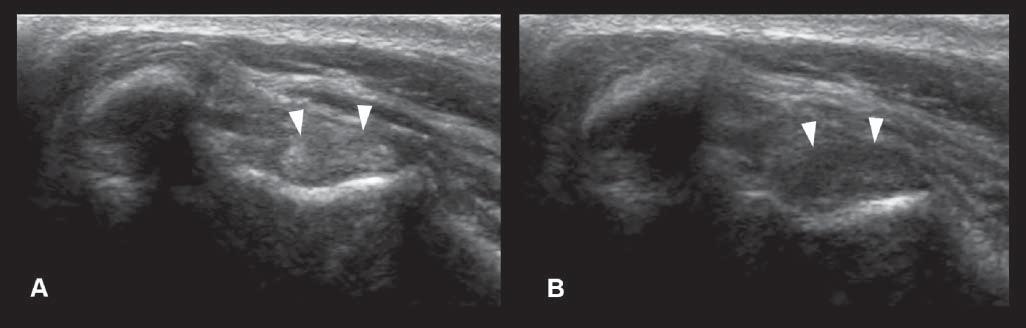

Anisotropy

Thisartifactismostcommonlydescribedinmusculoskeletalultrasoundandconsistsofadecreasein echogenicityofthestructure(suchasthetendonor ligament),duetoanobliqueposition(ratherthan perpendicular)oftheprobeonthebodypartbeing evaluated(Figure1.21).Thiscanbeeasilycorrectedby changingtheprobeangle.

Figure1.21. Anisotropy.A: Normalcross-sectionalappearanceofthebicepstendon(arrowheads),withtheprobebeing perpendiculartothestructure. B: Thedecreaseinechogenicityofthetendonisduetoanobliquepositionoftheprobe.This canbeeasilycorrectedbychangingtheprobeangle.Thisartifactcouldbemisinterpretedasacorelesion.